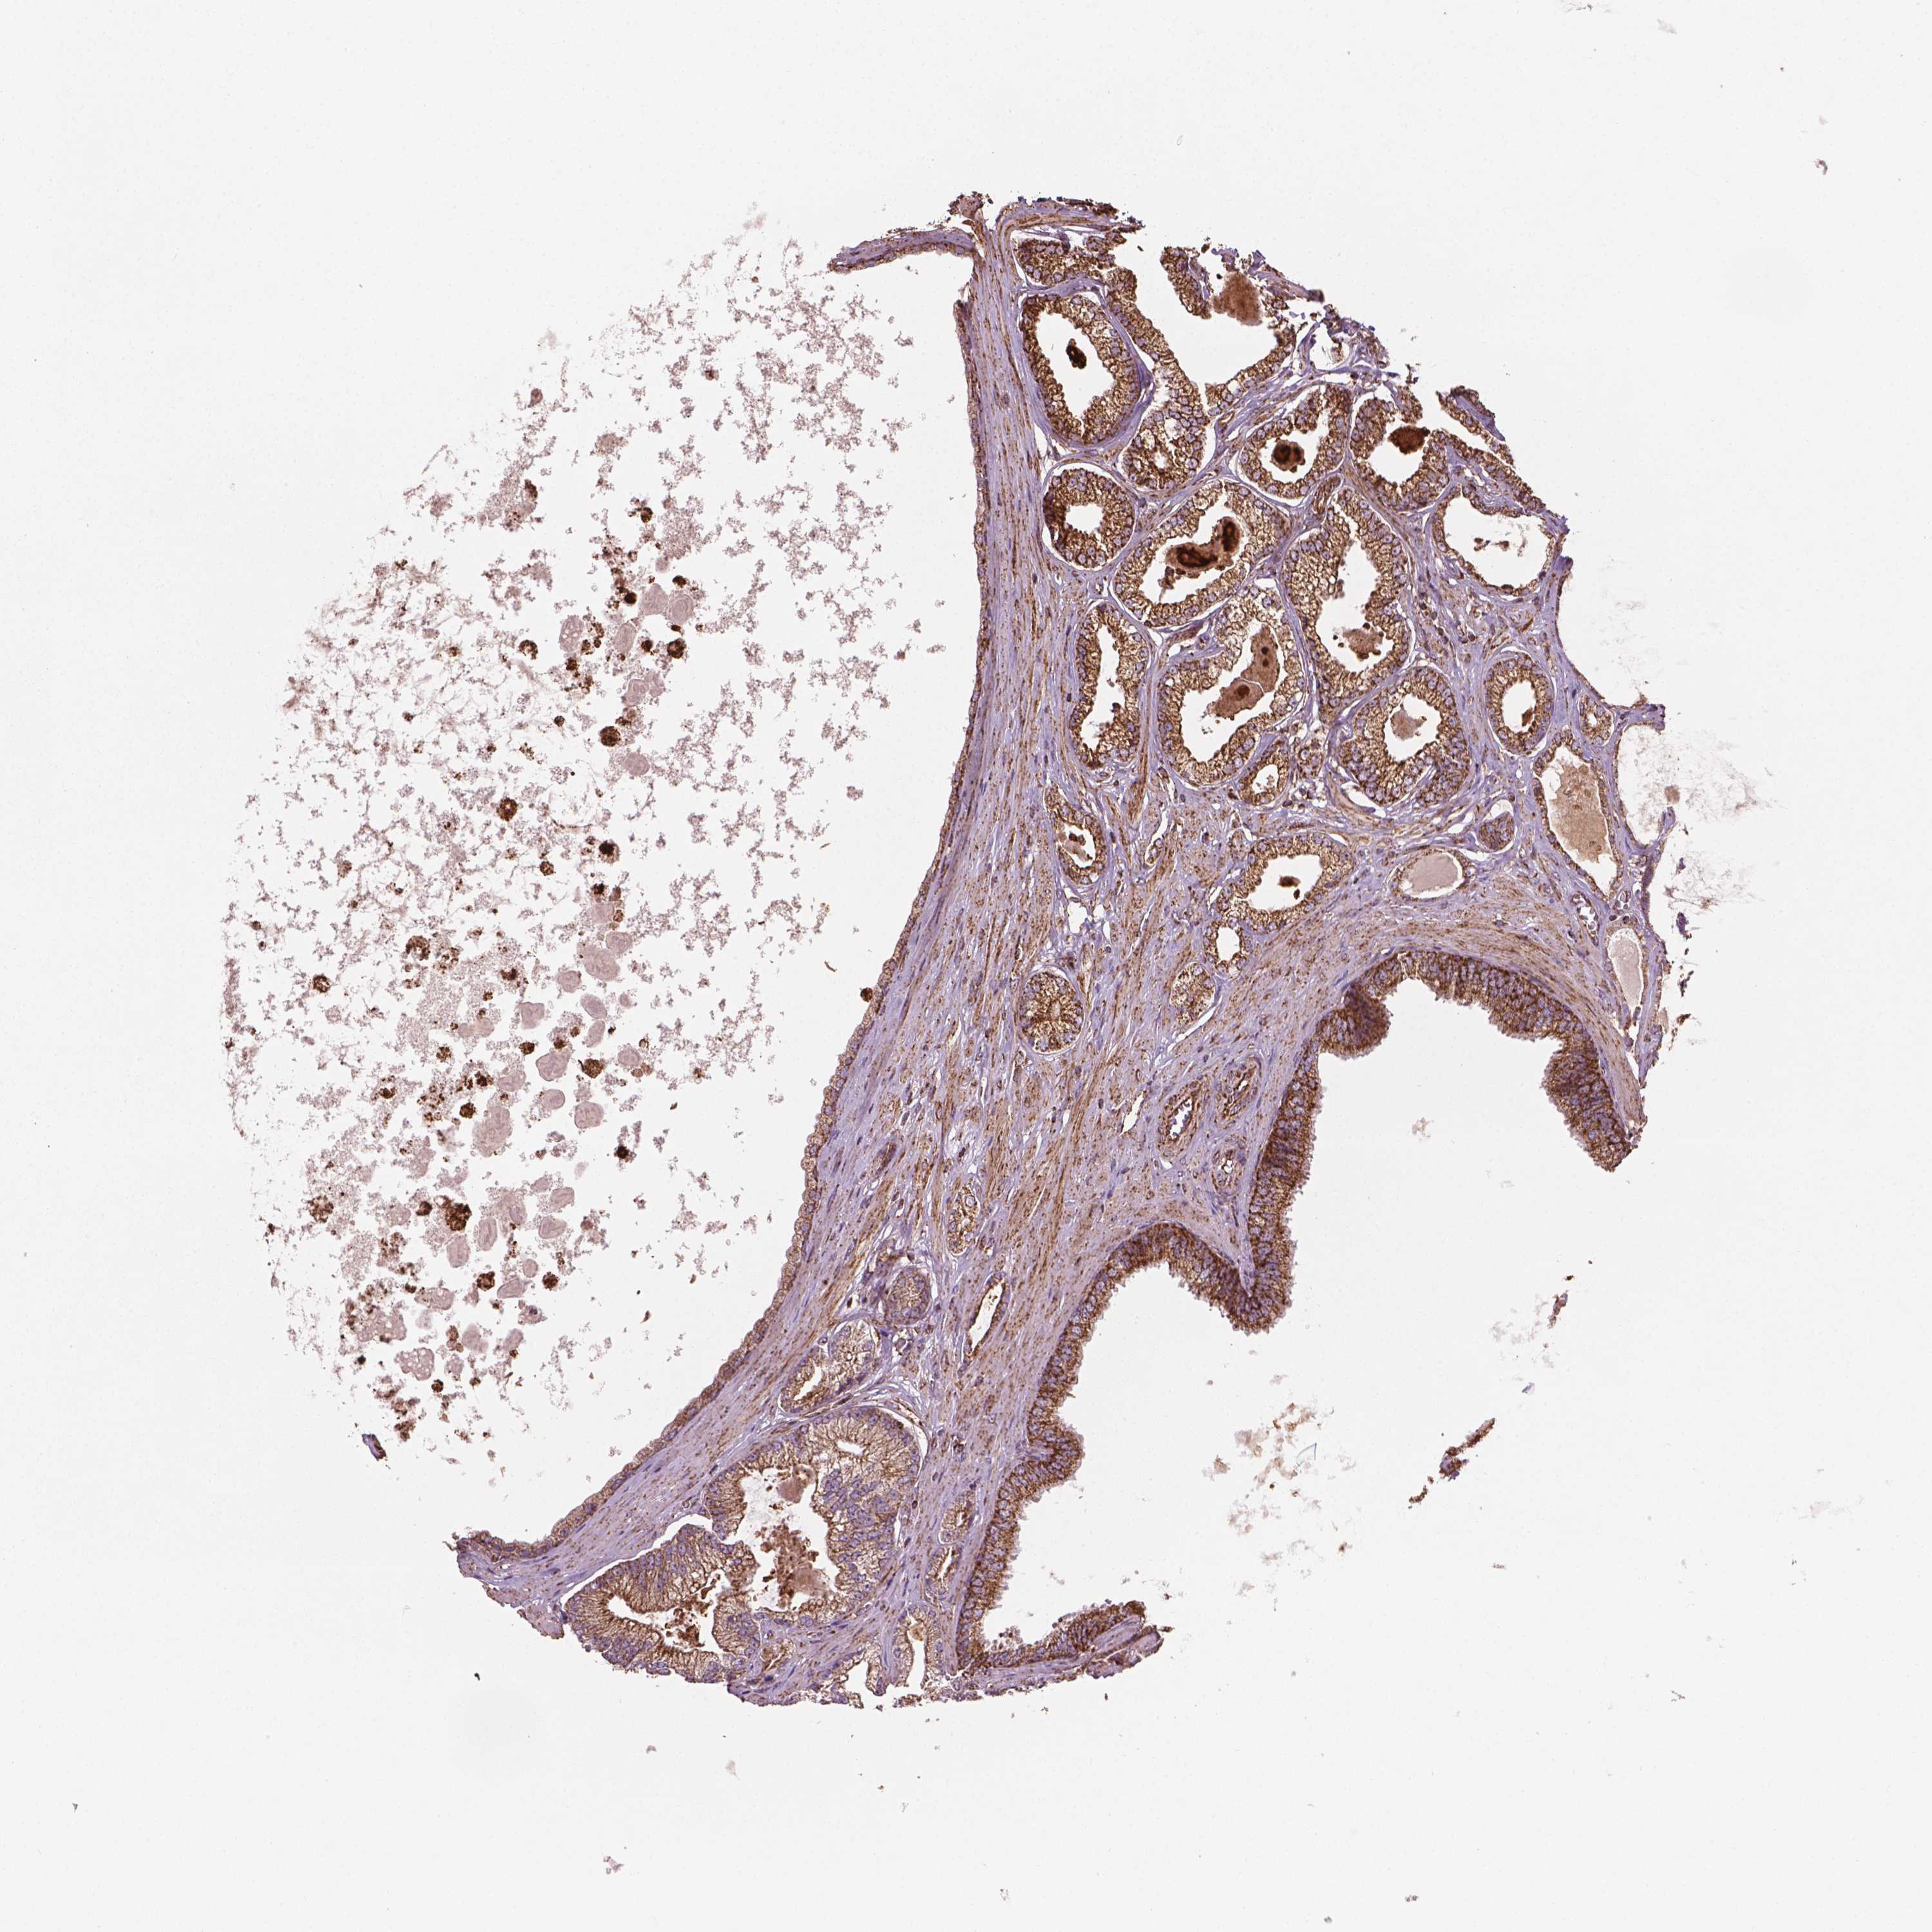

PROSTATE CANCER - Protein expressioni

A mouse-over function shows sample information and annotation data. Click on an image to view it in a full screen mode. Samples can be filtered based on level of antibody staining by selecting one or several of the following categories: high, medium, low and not detected. The assay and annotation is described here.

Note that samples used for immunohistochemistry by the Human Protein Atlas do not correspond to samples in the TCGA dataset.

Antibody stainingi

Antibody staining in the annotated cell types in the current human tissue is reported as not detected, low, medium, or high, based on conventional immunohistochemistry profiling in selected tissues. This score is based on the combination of the staining intensity and fraction of stained cells.

Each image is clickable and will lead to virtual microscopy that enables deeper exploration of all samples and also displays staining intensity scores, fraction scores and subcellular localization as well as patient and tissue information for each sample.

Antibody HPA071530

Staining

High

Medium

Low

Not detected

Intensity

Strong

Moderate

Weak

Negative

Quantity

>75%

75%-25%

<25%

None

Location

Nuclear

Cytoplasmic/membranous

Cytoplasmic/membranous,nuclear

Adenocarcinoma, High grade

Adenocarcinoma, NOS

Adenocarcinoma, Low grade